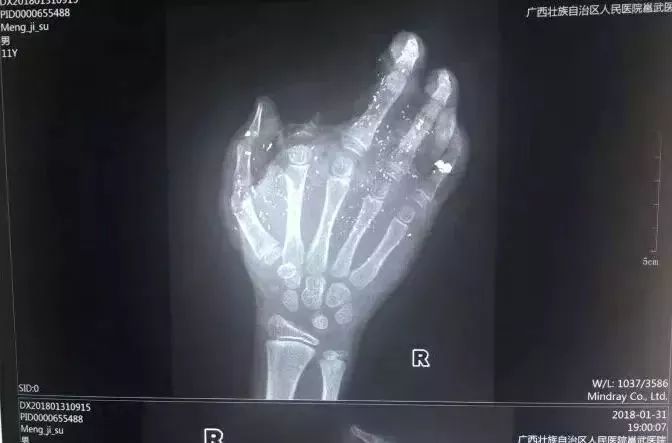

手机爆炸炸伤男孩手掌

2018年1月31日,广西也发生一起手机爆炸事件,小男孩手掌被炸得血肉模糊。

d8.jpg

孩子右手食指被炸没了,拇指、中指、无名指也都炸伤,经CT检查,右眼内还有2块手机碎片。据了解,手机之前出现过充电时发热现象,但家长当时没有在意。